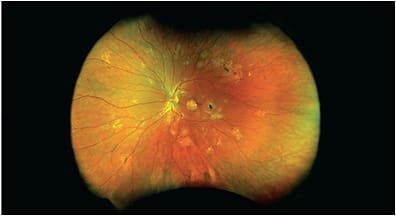

OPTOS

optomap single-capture UWF retinal imaging is making eye care more efficient. A 2021 study documented a 33% (28-minute) reduction in patient visit duration after implementing centralized optomap imaging.1 Others show that optomap uncovers 42% more pathology2 and optomap-guided OCT imaging impacted clinical decision making in 84% of cases.3